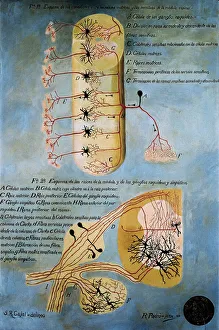

The central nervous system, the intricate network that governs our every thought and movement, is a marvel of complexity. From the delicate cerebellum tissue to the detailed light micrograph capturing its essence, we are reminded of its importance in maintaining balance and coordination. Anatomy comes alive as we explore the human brain from an inferior view. The intricacy of brain fibers is revealed through DTI MRI scans like C017/7099 and C017/7035, showcasing their vital role in transmitting information throughout this extraordinary organ. Artistic renderings bring us closer to understanding the medulla oblongata's significance within the brain. Its portrayal in various artworks allows us to appreciate how it controls essential functions such as breathing and heart rate. As we delve deeper into studying the central nervous system, models of the human brain provide invaluable insights into its structure and organization. Lateral views reveal countless regions responsible for cognition, emotion regulation, sensory perception, and motor control. Microscope slides offer glimpses into nerve cells' intricate architecture—a testament to their ability to transmit electrical signals at lightning speed. Meanwhile, glial stem cell cultures captured under a light microscope remind us of their crucial role in supporting neuronal function. Finally, artistic representations unveil the limbic system's enigmatic nature—an interconnected web responsible for emotions and memory formation. These captivating artworks allow us to visualize this complex network within our brains. Exploring these hints provides a glimpse into the awe-inspiring world of our central nervous system—the very foundation upon which our thoughts, actions, memories reside—reminding us just how remarkable our brains truly are.